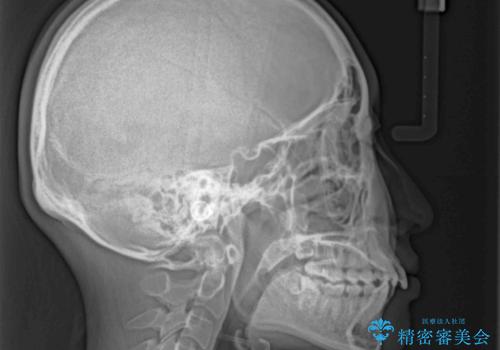

- 上顎前歯の突出感を気にして来院された患者様です。

上下左右第一小臼歯4本を抜歯して、積極的に口元を引っ込めるよう、ワイヤー装置にて矯正治療を行うこととしました。

抜歯矯正により、下唇が前方に突出した感覚が大幅に改善されました。